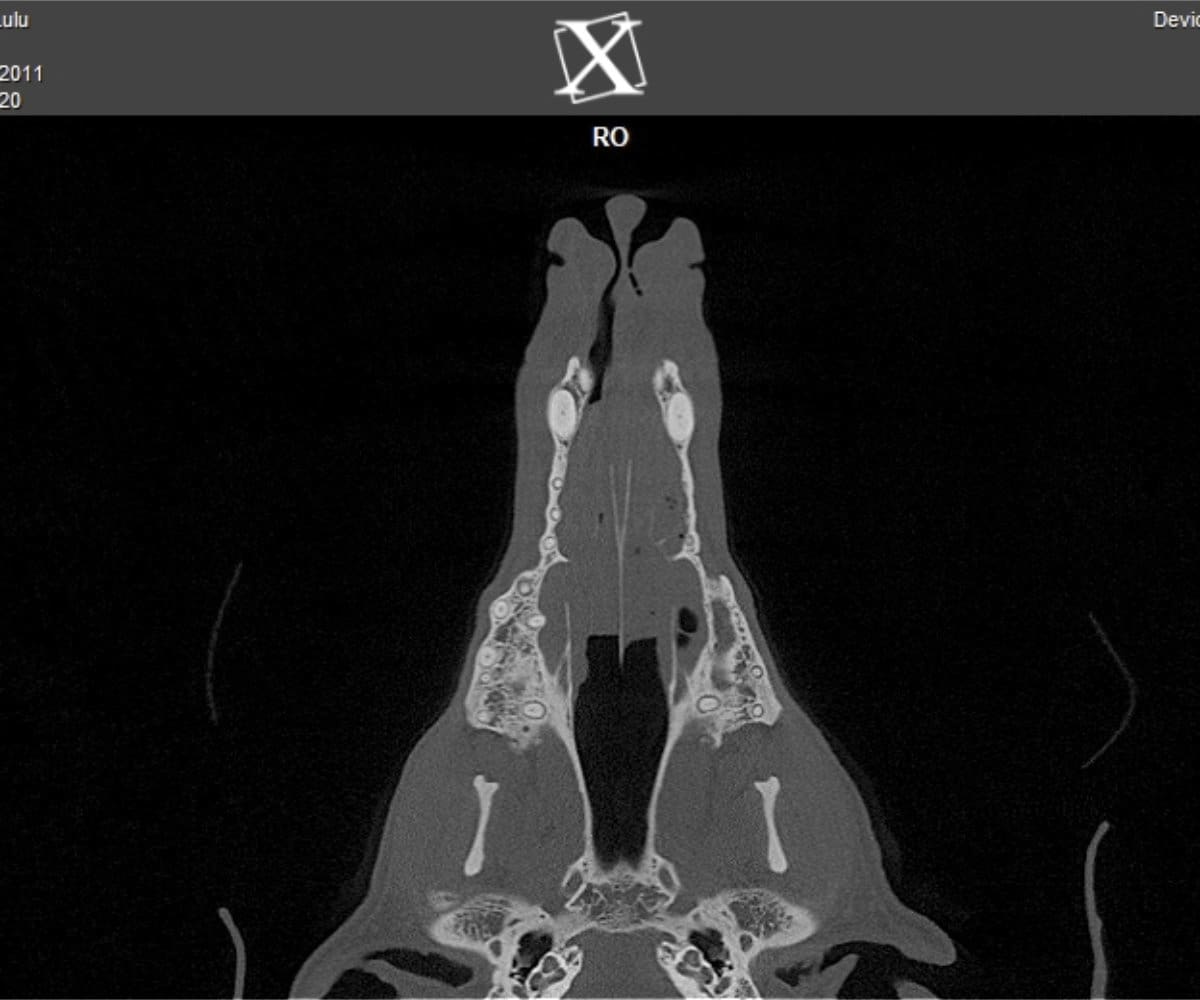

Animal Dental Care and Oral Surgery takes great pride in being at the forefront of veterinary care in Colorado, having introduced the pioneering cone beam computed tomography (CBCT) technology for our patients. While digital dental radiographs have been a cornerstone in veterinary dentistry diagnostics, providing invaluable insights into dental diseases in dogs and cats, they inherently present limitations as 2-dimensional images, often requiring considerable time during anesthesia.

In addressing these limitations, CBCT emerges as a pivotal advancement. Conducting a CBCT scan on our patients is characterized by minimal time and effort, effectively reducing anesthesia duration. Moreover, this technology facilitates the generation of a comprehensive 3D reconstruction of the teeth and skull, surpassing the constraints of traditional radiographs. This innovative approach empowers our veterinary professionals to identify oral pathologies that may have been missed on traditional radiographs.

Cone beam CT technology provides veterinarians with 3-dimensional images in far greater detail than dental radiographs. CBCT scans significantly decrease the amount of time a patient spends under anesthesia compared to the time it takes to complete dental radiographs.

Our CBCT VetCAT unit is easily rolled up to our treatment table and takes only 40 seconds to complete a scan. It has proven to be invaluable in the diagnosis and treatment planning for pets with periodontal, endodontic and cancerous disease conditions. It is also indispensable in the evaluating our trauma cases with jaw fractures.